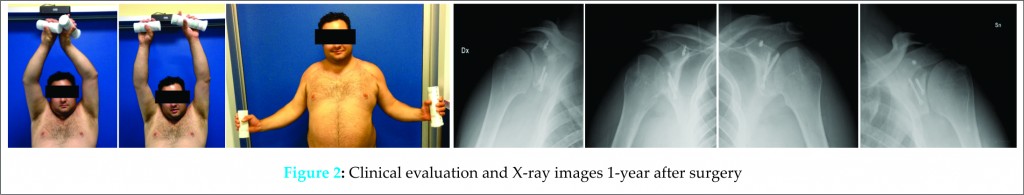

The surgeon suggested a step-by-step surgical treatment conscious about patient’s medical history and refusal of whatever blood transfusion for religious reasons. The first step was surgical treatment of dominant limb and then right side after 1 month. Surgical procedures were both performed under general anesthesia, beach chair position and fluoroscan aid. The deltopectoral approach was used and for both cases were evidenced a glenoid fossa deficiency with hypoplasia of scapular neck and glenoid. Bristow-Latarjet coracoid transfer procedure was performed to repair the anterior glenoid defect. Any posterior capsular release was performed. During surgeries, bleeding was controlled and intraoperative blood salvage was used to accommodate wishes of the patient to refuse homologous and autologous transfusions, as required his confession of faith. Through post-operatively management, shoulders were supported by a sling with 15° of abduction and maintained for 3 weeks. Passive and active movements of hand and elbow were early started. A 4 weeks later, clinical and radiographic evaluation were performed, and the patient was introduced to passive shoulder motion, while 2 weeks later he started an active controlled shoulder motion. He was followed for next 6 months by upper extremities therapist team. The 1 year after last operations, the patient was clinical and radiographical evaluated and he was able to perform left flexion up to 180° and 160 in right, bilateral abduction was 180 (Fig. 2). The constant score was 89 left and 83 right, disabilities of the arm, shoulder and hand (DASH) score was 17 left and 13 right and visual analogue scales were 0.